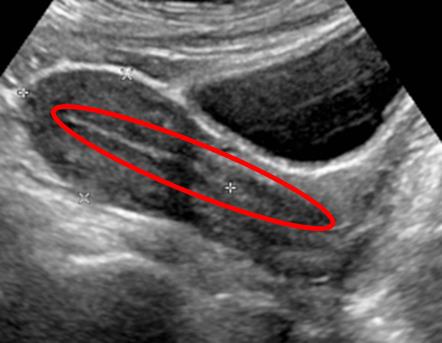

A 17-year-old girl presents to her pediatrician with a 6 month history of amenorrhea. She first started having irregular periods around 1 year ago. She had 1 period every 2 months until 6 months ago, when they ceased completely. Menarche was at age 12 and she is otherwise healthy. She enjoys running track and field and has been training for an upcoming meet. She denies alcohol use, smoking, and recreational drugs. She is not sexually active and does not take oral contraceptives. Her temperature is 36.7°C (98°F), blood pressure is 121/80 mmHg, pulse is 62/min, respirations are 11/min, oxygen saturation is 100% on room air, and BMI is 20 kg/m^2. Her pelvic exam reveals an anteverted uterus, no adnexal masses, a normal-appearing cervix with no cervical motion tenderness, and normal vaginal anatomy. An ultrasound is obtained and the results are shown in Figure A. Which of the following is the most likely cause of this patient's amenorrhea?

Figure/Illustration A is a pelvic ultrasound demonstrating an empty uterus with a closed myometrial cavity (red circle). This finding rules out pregnancy as a cause of amenorrhea.